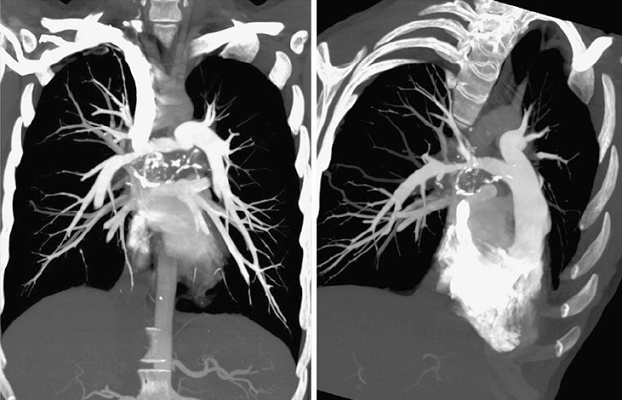

• La embolia pulmonar se diagnostica a partir de la descripción de los síntomas del paciente y se somete a investigaciones como ECG, cofre x -ray, una exploración de ventilación-perfusión (exploración V / Q) y una tomografía computarizada de los pulmones.